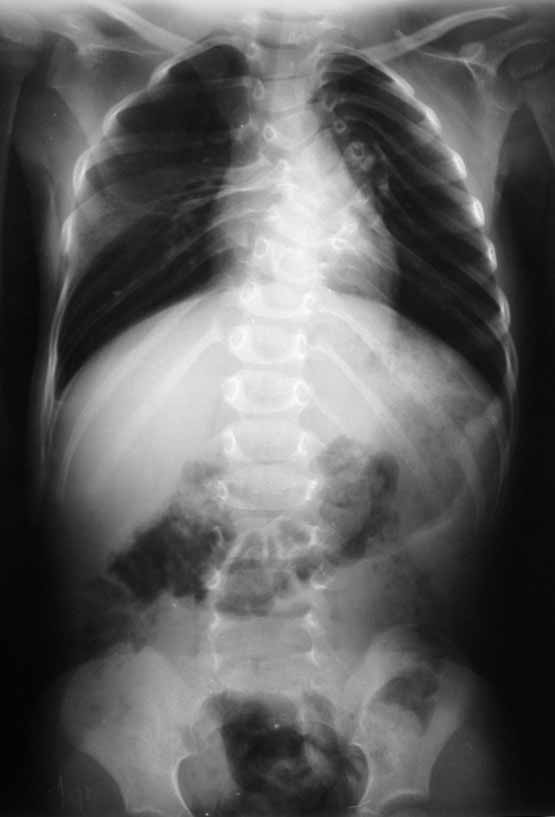

ДЗ: Врожденный S–образный сколиоз, аномалия развития позвоночника: клиновидные 5–6 грудные позвонки, аномалия развития грудной клетки: деформация ребер.

Анамнез заболевания: Болеет с рождения, начала ходить в 1,5 года. В 5 месяцев мама отметила наличие реберного горба, который увеличивался в размерах, в 1год 10 месяцев – произведена рентгенография позвоночника – отмечена его деформация.